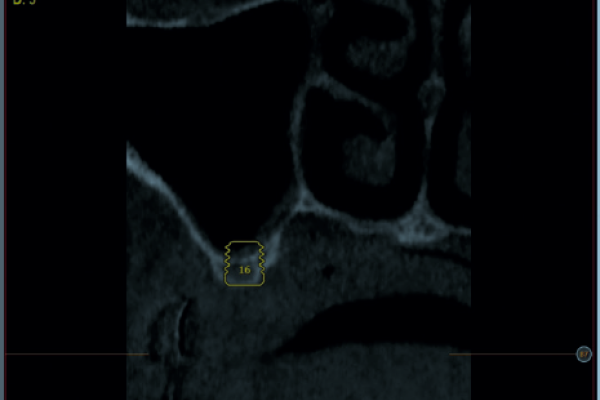

Implantes de 4,5 y 5,5 mm longitud insertados de forma directa en elevación crestal con hueso autólogo unido al Endoret-PRGF en alturas óseas residuales de 2-3 mm: estudio retrospectivo